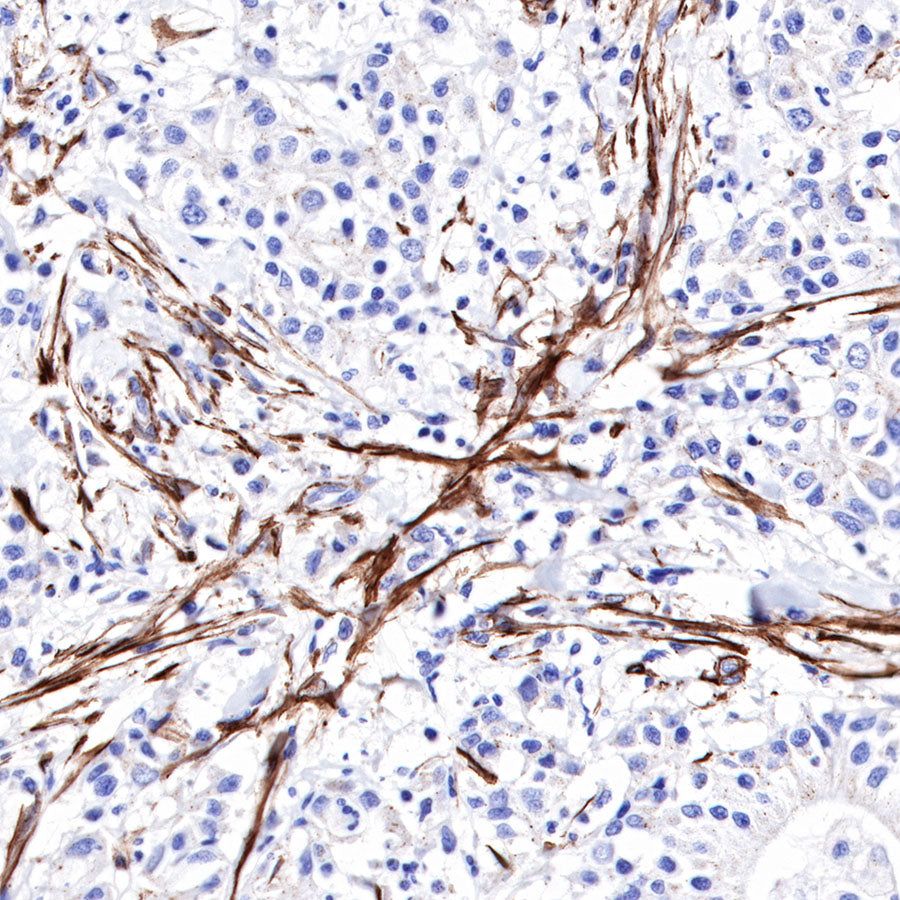

Immunohistochemistry